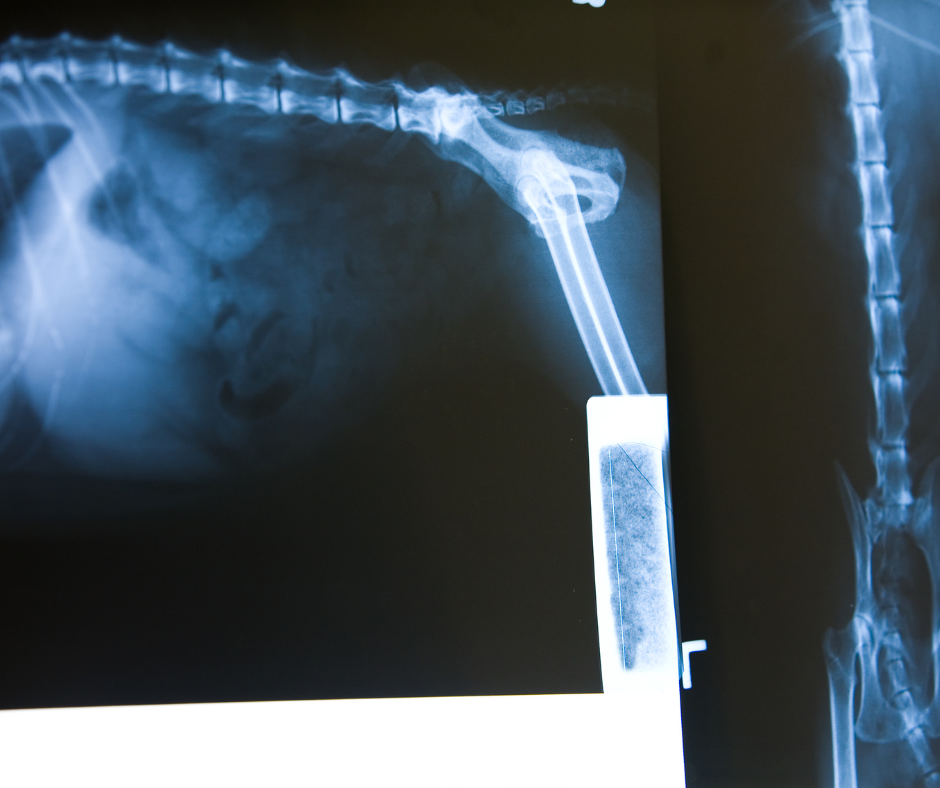

X-ray (Radiographs)

X-ray imaging is a critical diagnostic tool at Fernie Veterinary Services, which helps us see inside your pet’s body to identify a wide range of conditions, from broken bones to internal issues that may not be visible externally. Our X-ray machines allow us to take detailed images of your pet’s bones, organs, and tissues.

X-rays are commonly used to diagnose bone fractures, joint problems, arthritis, dental issues, and conditions such as pneumonia or heart disease. They are also essential for evaluating the presence of foreign objects or the extent of certain diseases, including cancer, affecting your pet.

The process of taking an X-ray is quick and non-invasive, and we ensure that your pet is as comfortable and stress-free as possible during the procedure. In some cases, sedation may be required to help your pet stay still, especially for pets that are anxious or in pain.